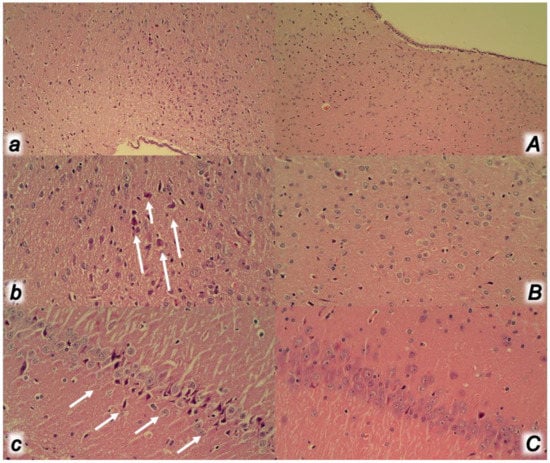

2.12. Microscopy

2.8. Brain Volume and Vessel Presentation Proportional to the Change in the Brain or Vessel Surface Area